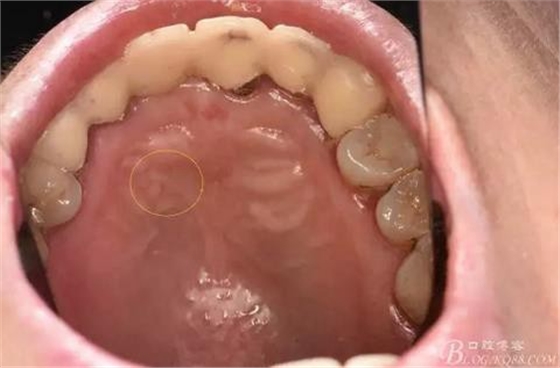

圖4.腭側(cè)觀:12根尖正對(duì)的腭粘膜隆起、有波動(dòng)感